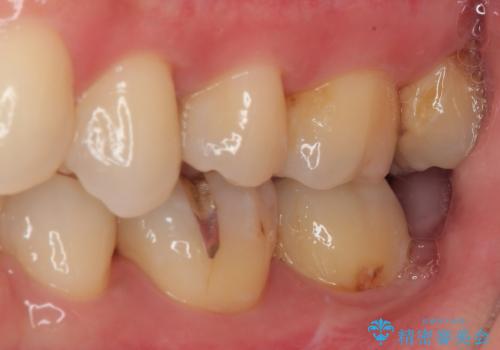

- 元々むし歯があったものの、処置が困難とのことでしたが、矯正治療を終えたので処置をしたいとのことで来院された患者様です。

左右ともに最後臼歯が頬側に顕著に突出しており、むし歯になってしまったことが想像されました。

矯正治療により処置が可能な位置に歯が移動したため、オールセラミッククラウンにて補綴治療を行うこととしました。

歯列が移動したとはいえ、左右ともに後方傾斜しており、むし歯の除去、形成(形を整える)、型取りの全てが非常に困難な処置となりました。